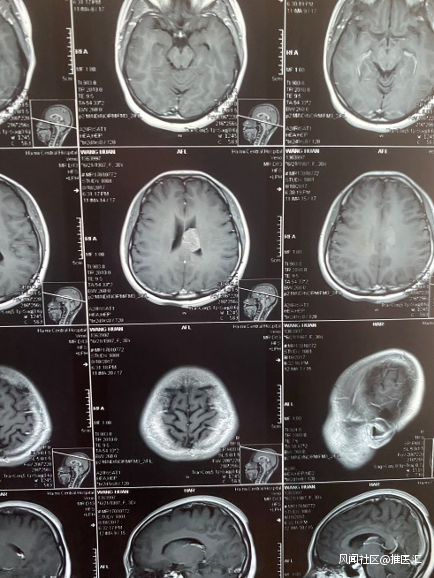

為了看得更清晰,醫生又讓我做了加強核磁共振。人生第一次做加強核磁共振。躺在診室裏只覺得天旋地轉,各種噪音吵得腦仁疼,而核磁共振的最終結果更是讓我腦仁疼。

果然有一顆又大又圓的瘤子四平八穩地橫躺在我的腦室中間。

影像結果丨作者供圖

文中作者因感到焦慮到精神衞生科就診,精神科醫生首先需要排除腦部器質性病變,才能夠診斷焦慮。不檢查不要緊,很多患者會在無意中發現腦部佔位,作者便是在頭顱CT檢查後發現了側腦室佔位,術後病理結果顯示是中樞神經細胞瘤。

中樞神經細胞瘤是生長於側腦室和第三腦室的小細胞神經元腫瘤,其主要發生部位在透明隔近室間孔處(Monro孔),引起臨牀症狀時,腫瘤均已長得很大。其主要症狀是頭痛和梗阻性腦積水所產生的顱內壓增高症狀。少見的中樞神經系統腫瘤,僅佔腦腫瘤的0.1%-0.5%,世界衞生組織(WHO)2000年公佈的中樞神經系統腫瘤中,中樞神經細胞瘤屬於神經元及混合神經元神經膠質起源的腫瘤,分級為Ⅱ級。

作者是幸運的,及早地發現了腫瘤,腫瘤位於側腦室,大小為4.5cm,尚未有顱內壓增高的症狀,因此作者的臨牀症狀不明顯。一旦病情延誤,患者可能會出現頭痛、噁心嘔吐等不適,且隨着腫瘤生長,上述症狀會進行性加重。